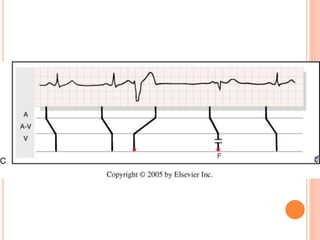

ATRIAL FLUTTER

 atrial rate = 250-350 cycles/min

 Ventricle rate is closer to 150, 100 or 75

beats/min

 2:1, 3:1 and 4:1

 F waves

 “sawtooth” shape